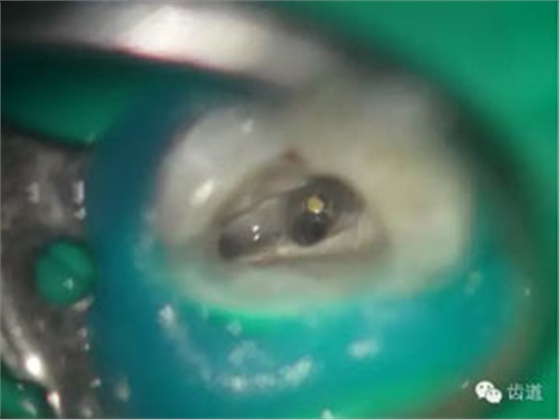

處理:顯微根管治療。放置橡皮障,去除暫封,顯微鏡下超聲去除頰側(cè)根管上段部分牙本質(zhì),探及遠(yuǎn)中根管口,見(jiàn)有糊劑遮蓋。Pathfile根管疏通,MTwo根管預(yù)備至2506#,配合3%次氯酸鈉和17%EDTA超聲蕩洗,干燥根管,放置氫氧化鈣糊劑,zoe暫封。